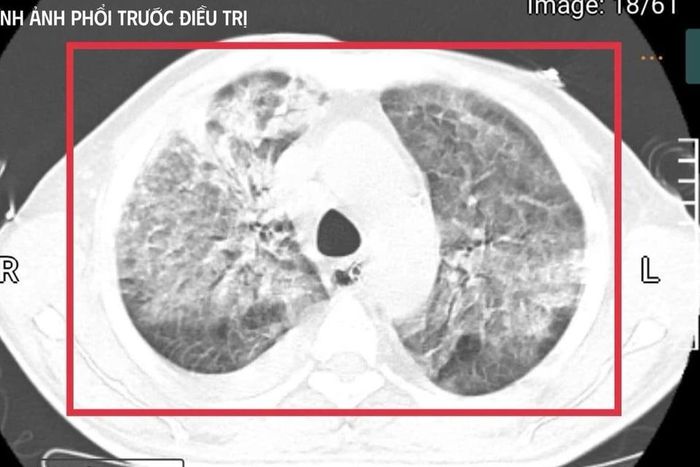

Hình ảnh phổi của bệnh nhân trước khi điều trị. (Ảnh: BVCC)

Ths.BSNT Nguyễn Kim Anh, khoa cấp cứu cho biết thời điểm tiếp nhận người bệnh là “khoảnh khắc rất căng thẳng”. Bệnh nhân hôn mê sâu, thang điểm Glasgow chỉ còn 9, mất phản xạ đường thở, phụ thuộc hoàn toàn vào máy thở. Nhiệt độ liên tục 41–42°C kèm run cơ toàn thân, gợi ý tình trạng tăng thân nhiệt ác tính trên nền nhiễm khuẩn huyết tối cấp.

Xét nghiệm cho thấy men gan và bilirubin tăng cao, rối loạn đông máu, creatinin tăng nhanh kèm vô niệu – biểu hiện của suy gan, suy thận cấp tiến triển. Nồng độ CK vượt quá 100.000 U/l, kèm đau cơ và nước tiểu sẫm màu, phù hợp với tiêu cơ vân cấp. Các chỉ số viêm như CRP, PCT tăng rất cao, phản ánh tình trạng nhiễm trùng – nhiễm độc toàn thân dữ dội. Trên nền đó là đái tháo đường chưa kiểm soát và viêm gan C mạn, khiến cơ thể người bệnh càng suy sụp.